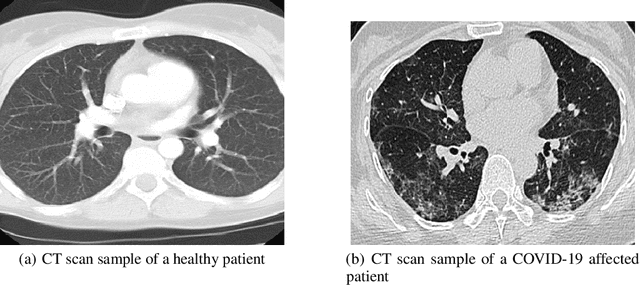

COVID-19 has been detrimental in terms of the number of fatalities and rising number of critical patients across the world. According to the UNDP (United National Development Programme) Socio-Economic programme, aimed at the COVID-19 crisis, the pandemic is far more than a health crisis: it is affecting societies and economies at their core. There has been greater developments recently in the chest X-ray-based imaging technique as part of the COVID-19 diagnosis especially using Convolution Neural Networks (CNN) for recognising and classifying images. However, given the limitation of supervised labelled imaging data, the classification and predictive risk modelling of medical diagnosis tend to compromise. This paper aims to identify and monitor the effects of COVID-19 on the human lungs by employing Deep Neural Networks on axial CT (Chest Computed Tomography) scan of lungs. We have adopted Mask RCNN, with ResNet50 and ResNet101 as its backbone, to segment the regions, affected by COVID-19 coronavirus. Using the regions of human lungs, where symptoms have manifested, the model classifies condition of the patient as either "Mild" or "Alarming". Moreover, the model is deployed on the Google Cloud Platform (GCP) to simulate the online usage of the model for performance evaluation and accuracy improvement. The ResNet101 backbone model produces an F1 score of 0.85 and faster prediction scores with an average time of 9.04 seconds per inference.